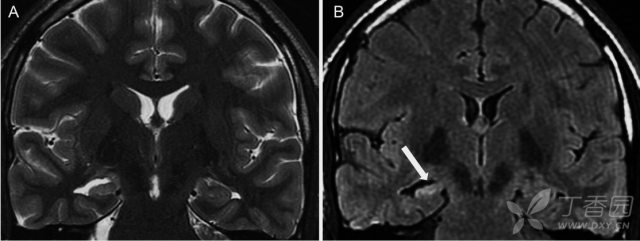

海马硬化的典型 MRI 特征为海马体积缩小,T2/FLAIR 信号增高和海马内部结构模糊,可伴有同侧的侧脑室颞角扩大、颞叶萎缩等。在颞叶癫痫伴海马硬化的患者 MRI 上常可出现同侧颞极的灰白质异常(「颞极模糊」),在 MRI 上表现为灰质与白质分界不清及 T2 高信号。需与单纯的海马萎缩、海马旋转不良相鉴别。海马旋转不良指单侧的海马旋转不完全,其形态异常,但内部结构混乱,但海马体积和信号正常。

图 1:31 岁难治性癫痫伴右侧海马硬化男性患者;A:T2WI;B:FLAIR;可见右侧海马高信号伴萎缩